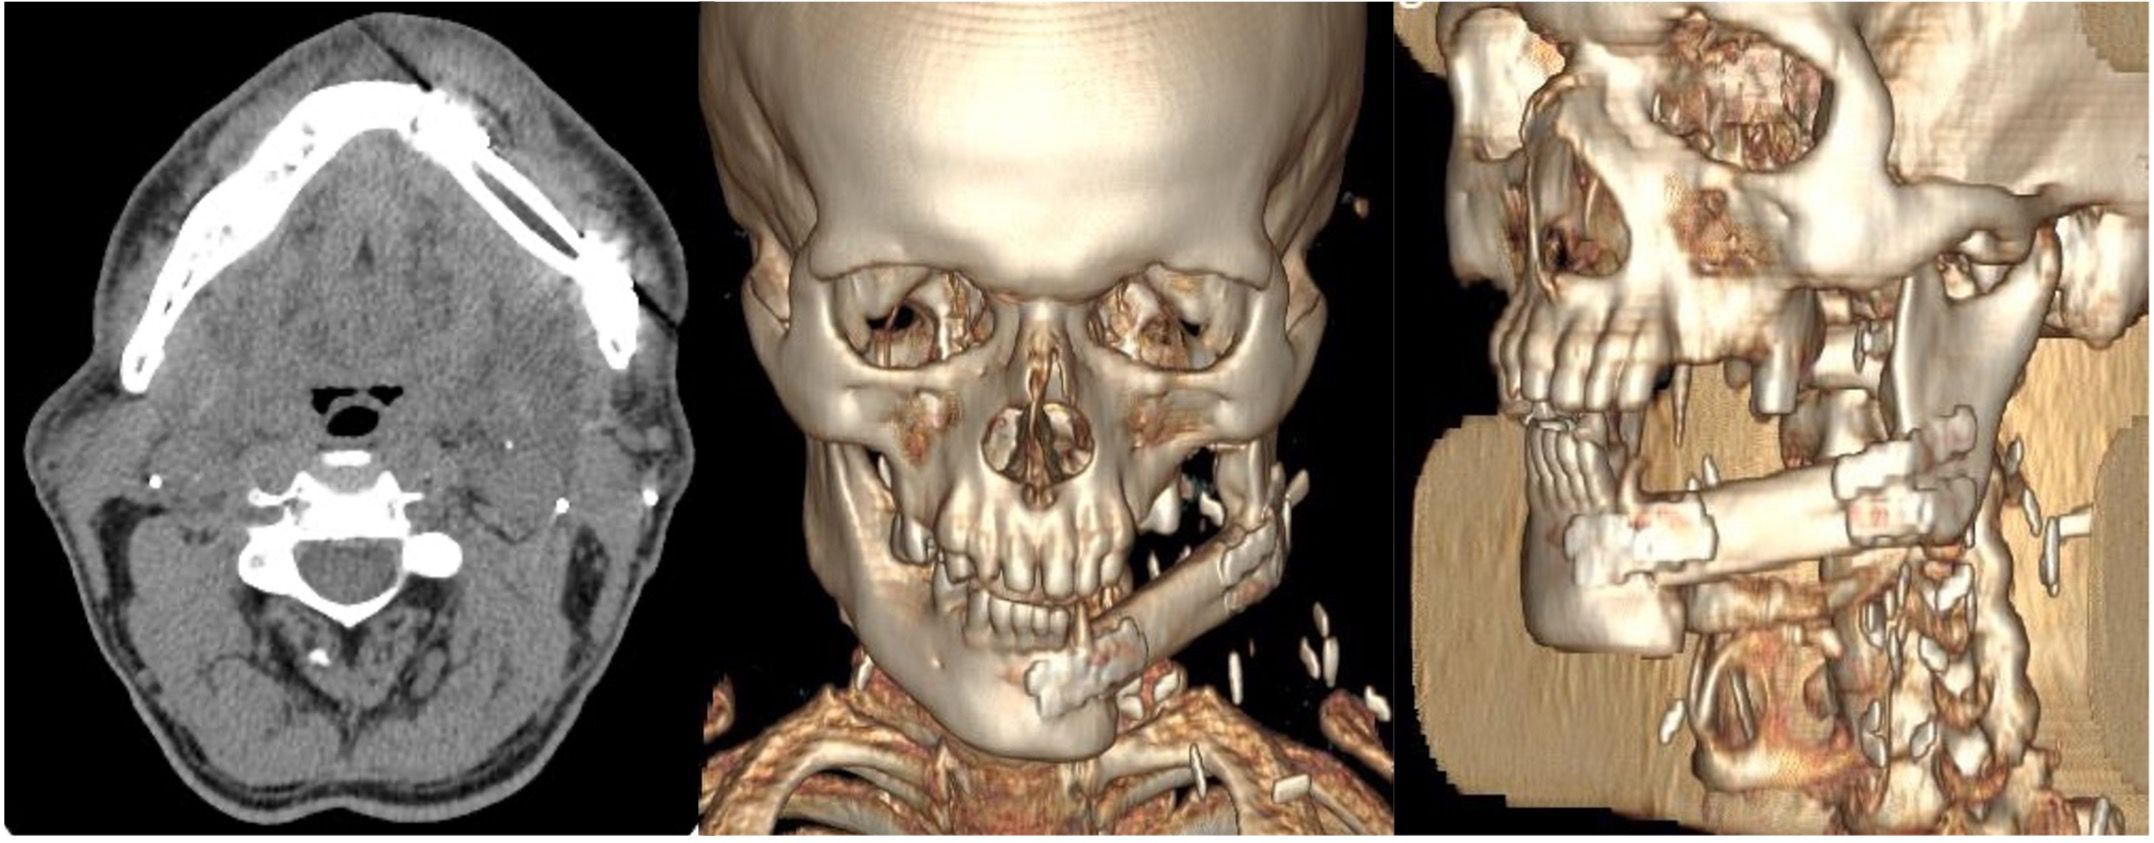

Following pedicle identification and division, the fibular flap underwent bench preparation to remove excess bone and lengthen the vascular pedicle while preserving periosteum. The fibula was positioned as a single segment extending from the symphysis to the left mandibular angle and secured with four 2.0 titanium compression miniplates and two screws per side (Figure 3).

Figure 3

Post-operative CT scans of the patient showing correct placement of the free fibula flap to reconstruct the left hemimandibular defect. The flap is secured with miniplates to the residual mandibular segments and positioned superiorly at the level of the alveolar crest to ensure optimal future implant rehabilitation.